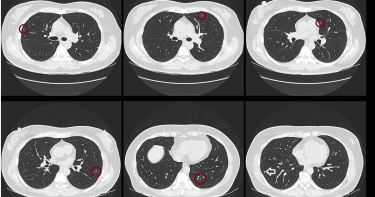

一名60歲女子的肺結節1年內從1顆暴增至10顆,就醫電腦斷層一照猶如「滿天星」。醫師蘇一峰追問得知,女子常在不通風的浴室使用漂白水,或是密閉的車內噴灑酒精,揪出病因之後,立刻給她適當的消炎藥物治療。蘇一峰在臉書表示,女子去年檢查發現一顆肺結節,就在某間醫學中心定期追縱,結果今年電腦斷層一照,發現原本只有一顆的肺結節,居然變成10顆的「滿天星」,還被該院門診的醫師打氣,提醒半年後要回來追蹤病情,說不定會開刀。後來蘇一峰問診得知,女子的肺結節數量增加竟是錯誤的生活習慣導致,對方想到近來多種病毒肆虐,常在不通風的浴室使用漂白水,或是密閉的車內噴灑酒精,後來甚至有些胸悶想要咳嗽。蘇一峰指出,過量的消毒液一旦揮發,具有「肺呼吸道毒性」,肺部發炎也會導致肺結節,但他強調,只要找出病因就能處理,除了立即教導女子正確的消毒觀念,也有給予適當的消炎藥物治療。